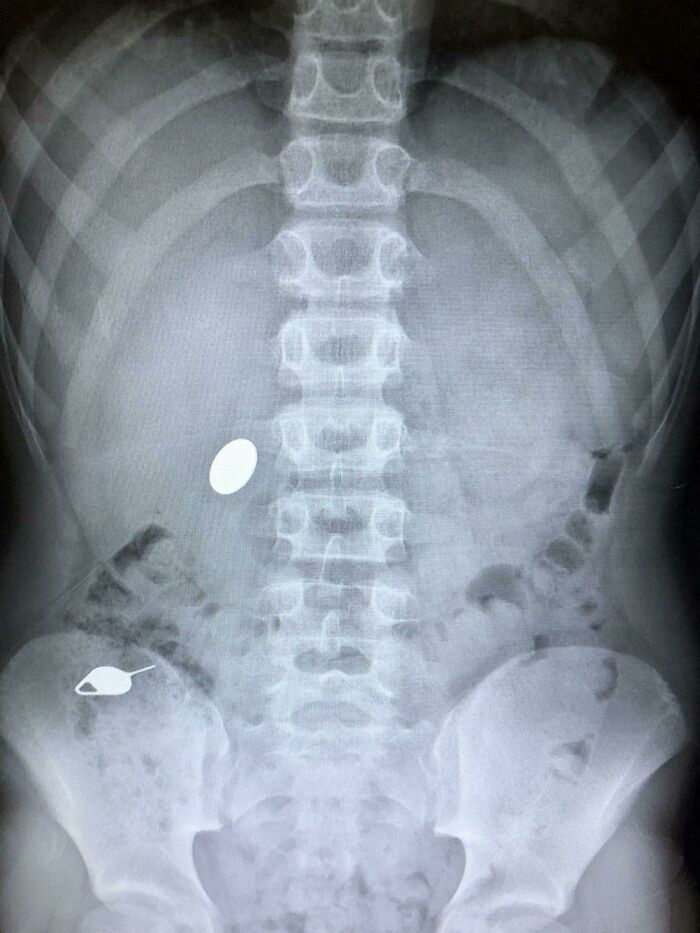

Mi hijo se tragó una moneda mientras le enseñaba a su hermano pequeño cómo se había tragado accidentalmente una llave SIM el día anterior